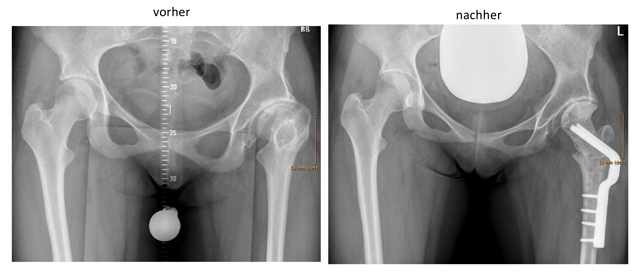

Die Proximale Femur Osteotomie bezeichnet die Achskorrektur am oberen Teil des Oberschenkelknochens. Meist sind Drehfehler (Knochentorsion) und Abweichungen des Schenkelhalses in X-Richtung Grund für die Operation.

Die häufigst durchgeführte Technik der Proximalen Femur Osteotomie geschieht mittels chirurgischem Zugang von der Außenseite des Oberschenkel. Nach Durchtrennung des Knochens und Neupositionierung in der gewünschten Position wird die erzielte Korrektur mittels Schrauben-Platten-System gehalten, ähnlich wie bei einem Knochenbruch.

Intertrochantäre Ostetomie